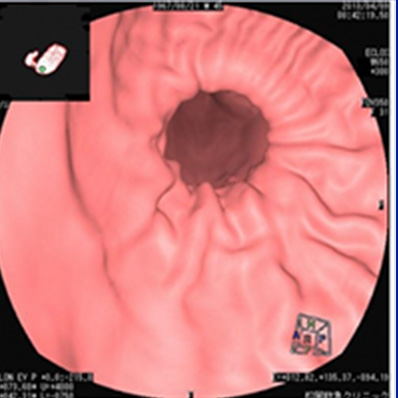

仮想胃内視鏡

胃ポリープ

以前より画質が向上しました。

細かい病変まで探せます。